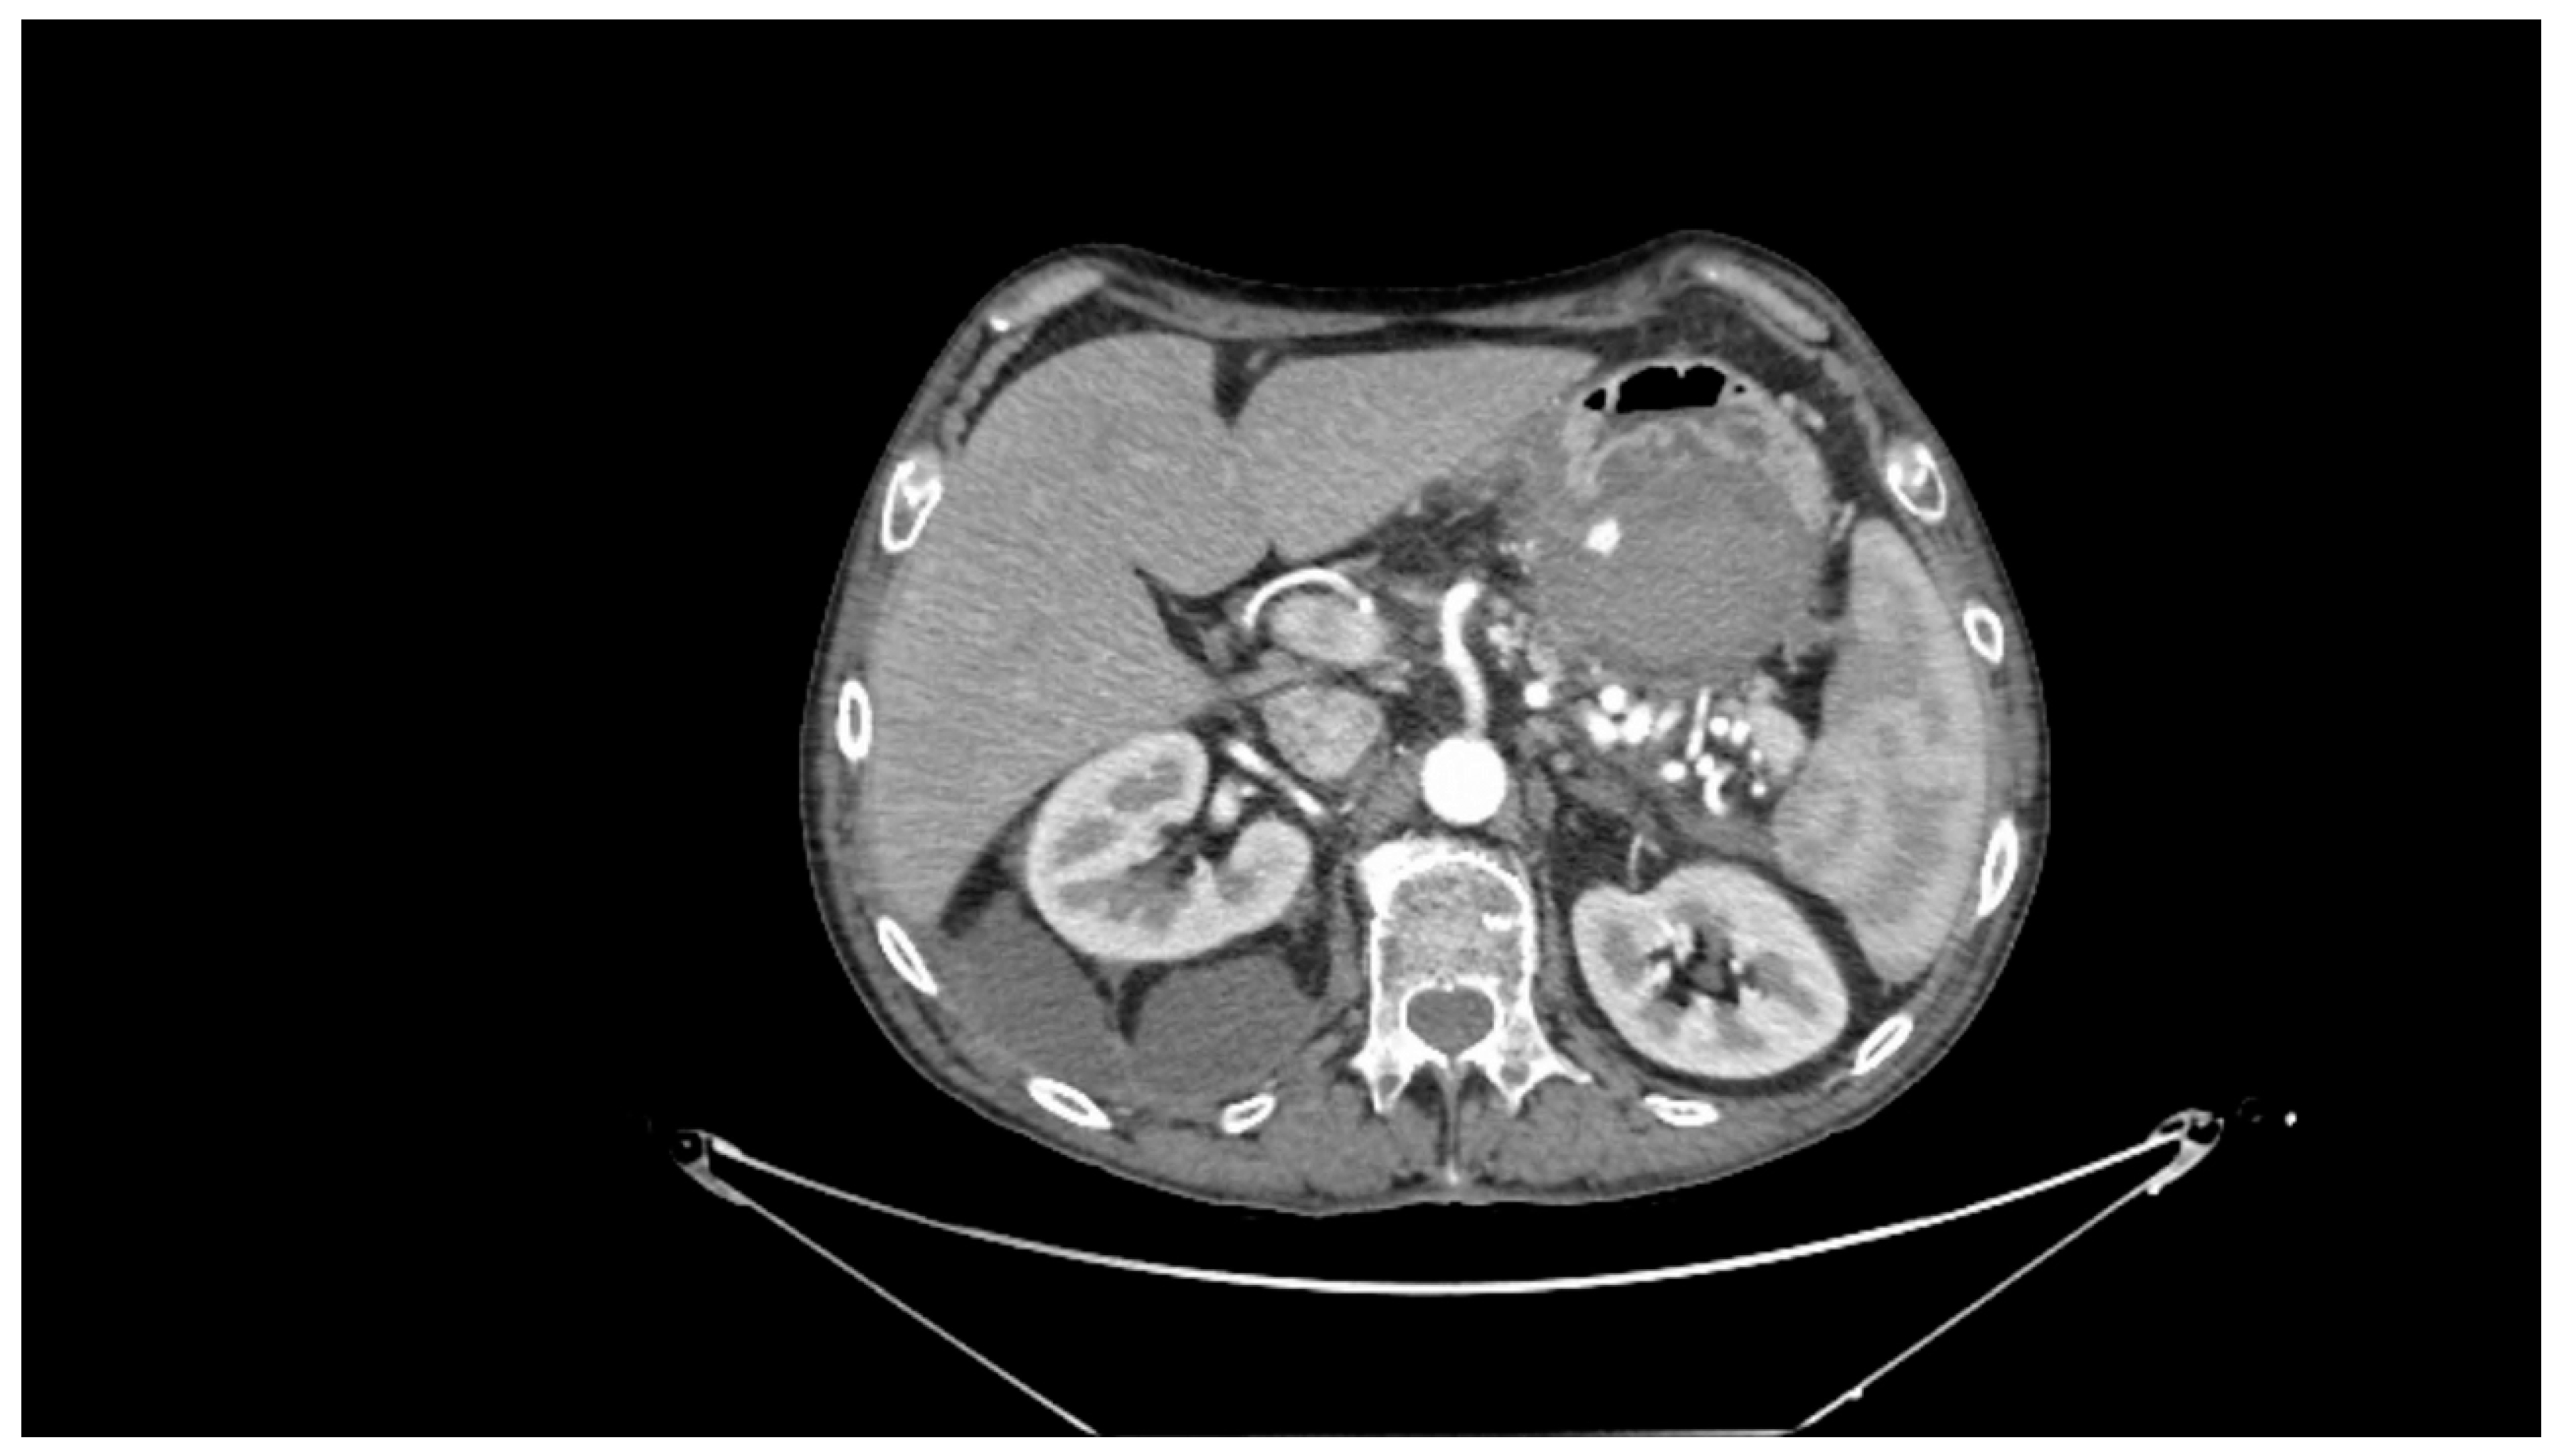

Contrast-enhanced CT scan remains a fundamental study for diagnosing complications of pancreatitis, including bleeding [31]. In cases of acute hemorrhagic pancreatitis, unenhanced CT typically shows significant enlargement of the pancreas with areas of low attenuation. After intravenous contrast administration, the pancreas displays irregular contrast enhancement, indicating areas of normal perfusion (i.e., viable parenchyma) and regions of reduced or abnormal perfusion (i.e., suggesting edema or necrosis) [21,31,39]. In cases of direct vascular damage or intraluminal bleeding, extravasation of contrast material can be seen, a highly specific finding for active bleeding (Figure 2) [31,40].

Figure 2.

Contrast-enhanced abdominal computed tomography showing active bleeding inside a peripancreatic collection. Reproduced with permission from Bellio, G., et al. [29].